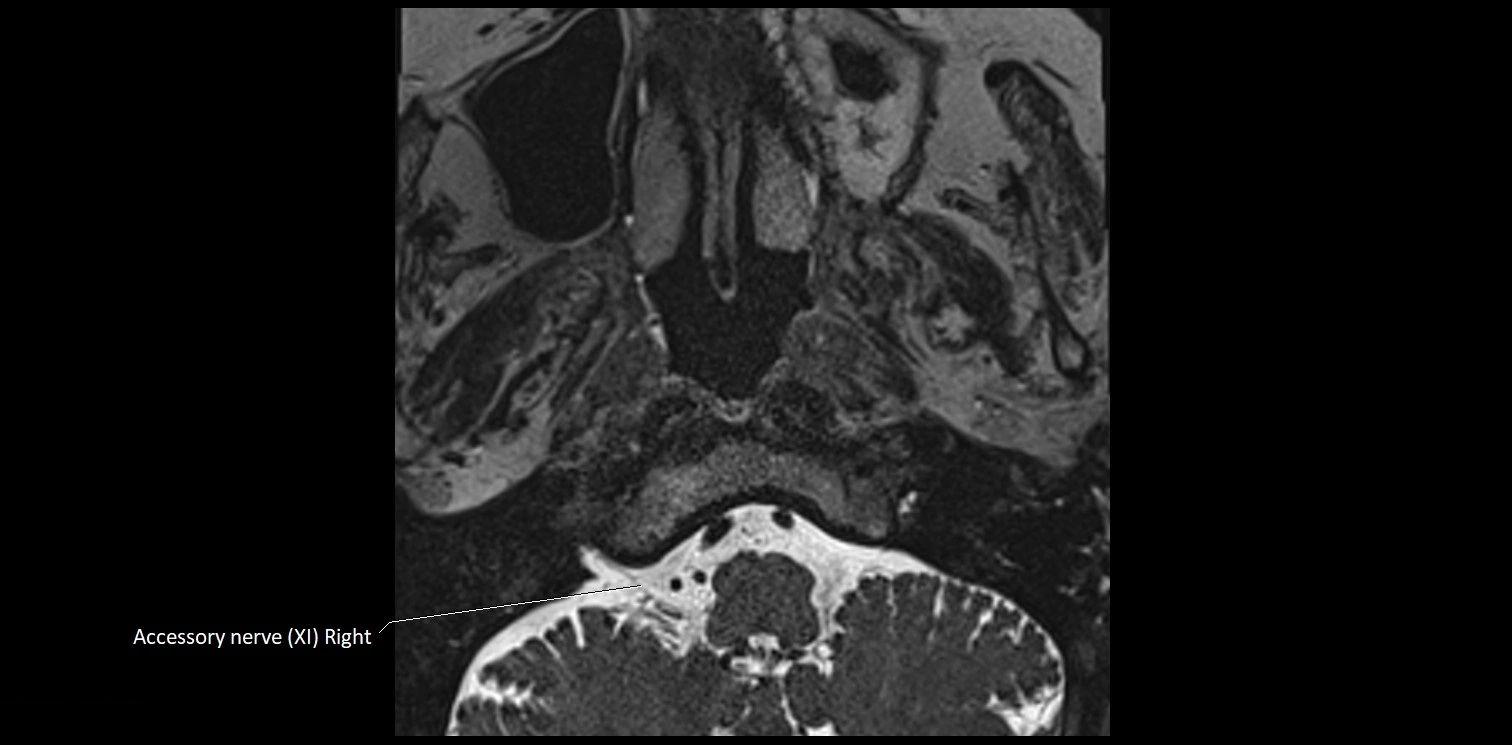

MRI images

image